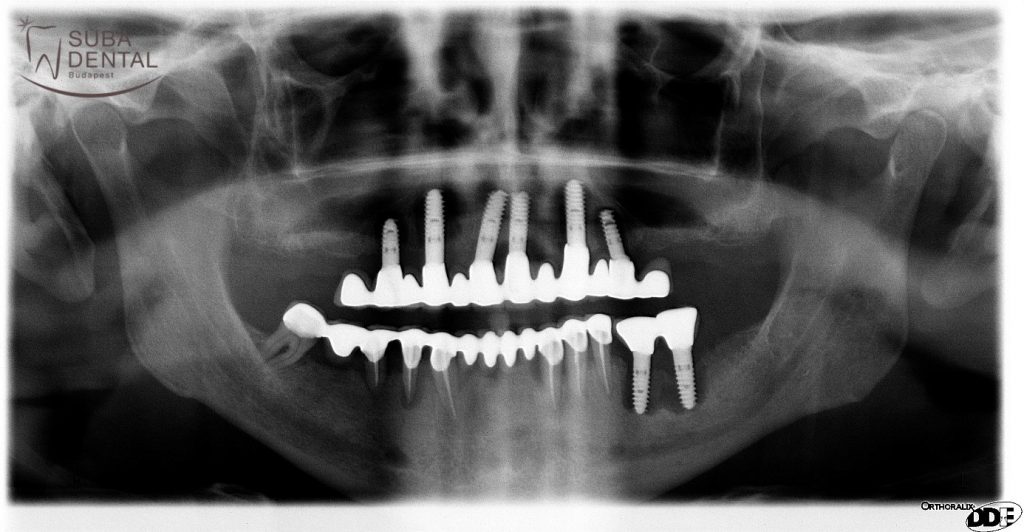

- Amennyiben a régi implantátumok körül gyulladás látszik, periimplantitisre utaló klinikai vagy radiológiai tünetek vannak (vérző, gyulladt íny, fájdalom, csontfelszívódás, genny ürül az implantátum mellől), a fogorvos azonnal kérhet egy 3 dimenziós CBCT röntgenfelvételt. Sajnos az is előfordulhat, hogy nemcsak a koronát, hanem az egész implantátumot el kell távolítani a kezeletlen periimplantitis okozta fertőzés miatt!

A jobb oldali felső utolsó implantátum menthetetlen volt a körülötte kialakult gyulladás és csontveszteség miatt

Bal alsó úgynevezett penge implantátum körül teljesem felszívódott a csont. Sürgősen el kellett távolítani, mivel gennyes, fájdalmas volt

Rendszeres ellenőrzés elmulasztása miatt minden implantátumot el kellett távolítani, mert mindegyik körül úgynevezett periimplantitis alakult ki

Implantátum körüli gyulladás intraorális röntgenfelvételen